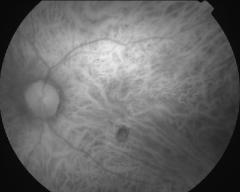

IM000007

IM000008

IM000009

IM000010

IM000011

IM000012